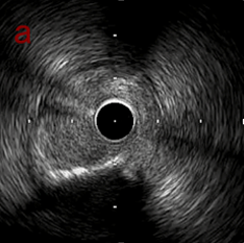

IVUSでは8時方向からPD枝がはいいてくる。

PreのIVUSではaの部位のみlipid plaqueを認め削ることでdistal embolismのリスクがあり、そのほかは270度の偏心性石灰化であるがwire biasは良好。